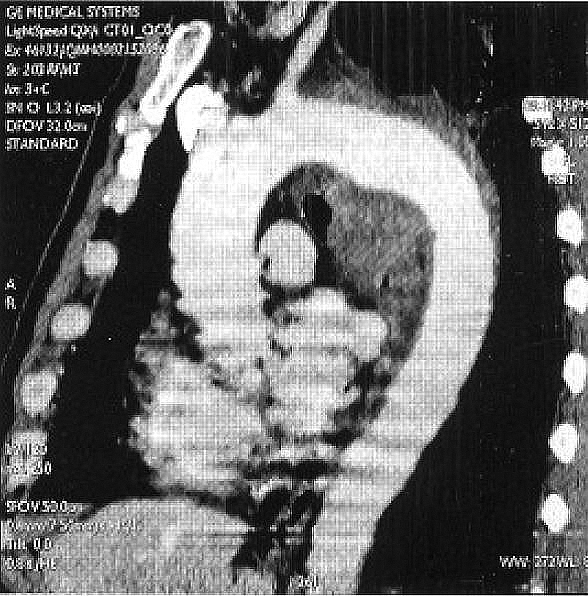

ontrast CT thorax showed a large para-mediastinal mass in the left upper lobe in connection with the aortic arch (Figure 3). There was direct communication between the mass and the aortic lumen via a large focal luminal defect. The large periaortic haematoma extended into the posterior mediastinum, encasing the descending aorta and esophagus (Figure 4). The mass was closely associated with and surrounding the apico-posterior segmental bronchus, with infiltration of adjacent lung parenchyma. The rest of the aorta was pristine without aneurysmal dilatation, dissection or atheroma.

Figure 4: CT thorax showing a large periaortic haematoma